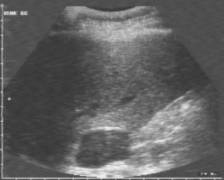

Data inserimento: 28/12/2004

Data esame: 23/12/2004

Strumento: Sonosite

Età paziente: M 64 anni

Neoformazioni surrenaliche bilaterali di maggiori dimensioni al surrene sinistro, asintomatiche.

Elaborazione digitale: Andrea Dini

In collaborazione: Dr. Davide Agostini, Dr.ssa Ornella Orsini